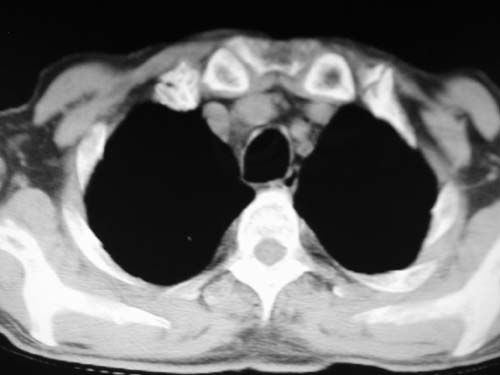

男,80岁

肺动脉段突出,左右肺门不等大,左肺门明显增大,肺动脉干及左肺动脉明显增宽,考虑先天性肺动脉狭窄瓣膜狭窄型。

左肺动脉异常增粗,考虑肺动脉狭窄可能。

右肺上叶继发性肺结核。

右侧胸膜增厚、钙化,左侧胸膜反应。